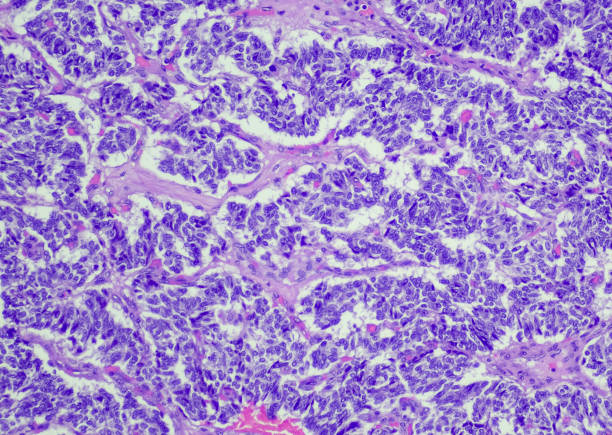

정확한 췌장암 초기증상 검사법

정확한 췌장암 검사를 위해선 내시경 초음파, CT 스캔, MRI 스캔 등의 고급 검사법을 고려해야 합니다.

내시경 초음파는 내시경을 통해 췌장을 직접 확인하며, CT와 MRI는 더 자세한 영상을 제공하여 췌장암을 발견하는 데 도움이 됩니다.

특히 MRI는 X선 노출이 없고, 조영제를 사용하지 않아도 되기 때문에 안전한 옵션 중 하나입니다.